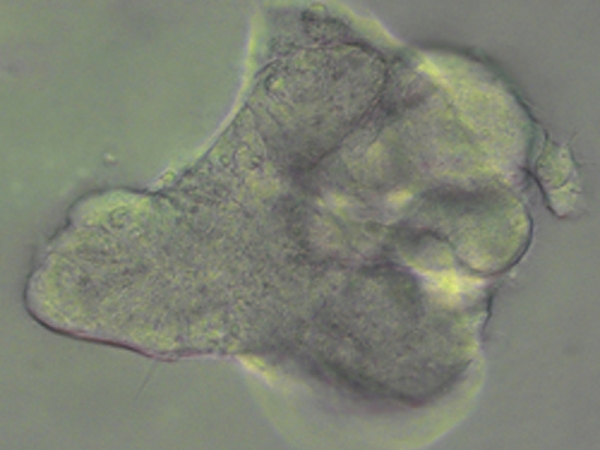

Từ những tế bào da của bệnh nhân xơ nang phổi, các nhà khoa học trường địa học Cambridge đă chế tạo thành công cụm tế bào mô phỏng các chức năng của lá phổi bị bệnh. Kết quả của nghiên cứu này sẽ là tiền đề giúp giải quyết vấn đề sức khỏe của bệnh nhân mắc bệnh xơ nang phổi. Bằng cách quan sát lá phổi mini này hoạt động, các bác sĩ sẽ có góc nh́n chính xác hơn về diễn biến của bệnh và t́m ra loại thuốc đặc trị trên một quy mô nghiên cứu lớn hơn.

Nghiên cứu được thực hiện đối với một chúng xơ nang phổi điển h́nh (chiếm 75%) gây nên bởi một đột biến trong gen CFTR, thường gọi là là đột biến delta-F508. Các tế bào được lấy từ da người bệnh sẽ được tái lập tŕnh tới trạng thái đa năng cảm ứng (induced pluripotent state - ở trạng thái này các tế bào có thể phát triển thành bất cứ loại tế bào nào trong cơ thể) và trở thành các tế bào đa năng cảm ứng (iPS - induced pluripotent stem). Sử dụng các tế bào loại này, các nhà khoa học tái tạo lại sự phát triển của phôi phổi trong pḥng thí nghiệm bằng cách kích hoạt một quá tŕnh h́nh thành phôi dạ (gastrulation) theo đó các tế bào này sẽ tạo thành các lớp bào riêng biệt bao gồm đầu tiên là các nội b́ sau đó là ruột trước (foregut), từ đó h́nh thành nên lá phổi. Tiếp sau đó, những tế bào này sẽ tiếp tục được kích thích để phát triển thành mô đường hô hấp ngoại biên (the distal airway), phần của phổi chịu trách nhiệm luân chuyển khí và thường liên quan đến các bệnh như xơ nang phổi hay một số dạng ung thư phổi.

Sau mỗi cuộc thử nghiệm với một loại thuốc tiềm năng, để có thể kiểm chứng khả năng hoạt động của những chiếc phổi mini này, các nhà nghiên cứu sử dụng một loại thuốc nhuộm huỳnh quang nhạy cảm với sự có mặt của clorua. Nếu những lá phổi mini hoạt động tốt, chúng sẽ cho phép clorua đi qua và do vậy chất huỳnh quang sẽ đổi mầu. Ngược lại, chất huỳnh quang sẽ không thay đổi, điều này đồng nghĩa với việc loại thuốc thử nghiệm là không có tác dụng.